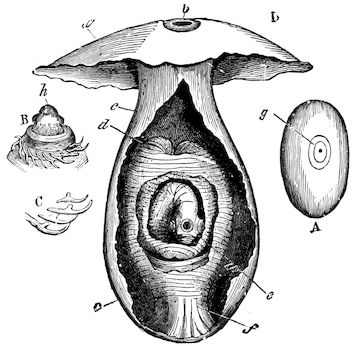

Fig. 1.—Rachitis in a young goat.

Fig. 1.—Rachitis in a young goat.